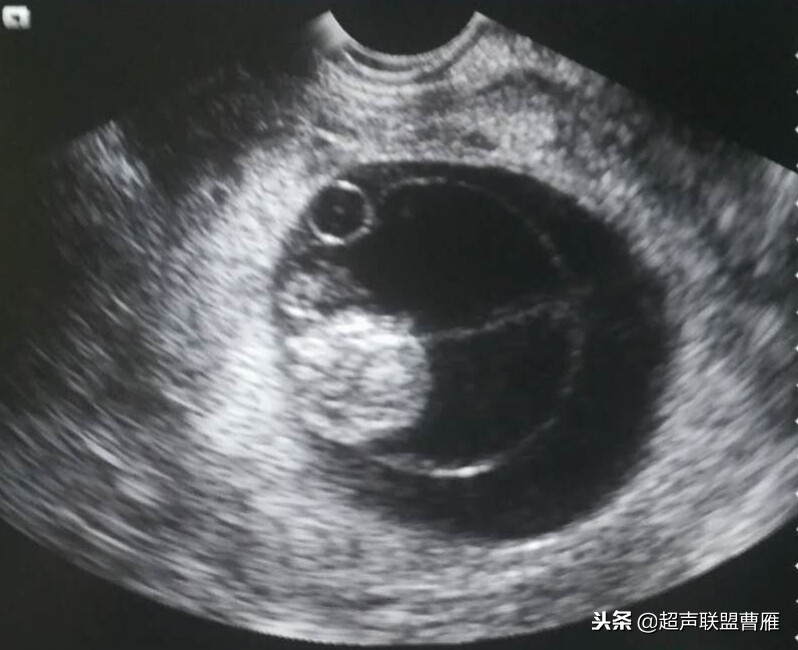

一个孕囊有两个卵黄囊,单卵双胎。

两个孕囊各有一个卵黄囊,双卵双胎,HCG应该更高。